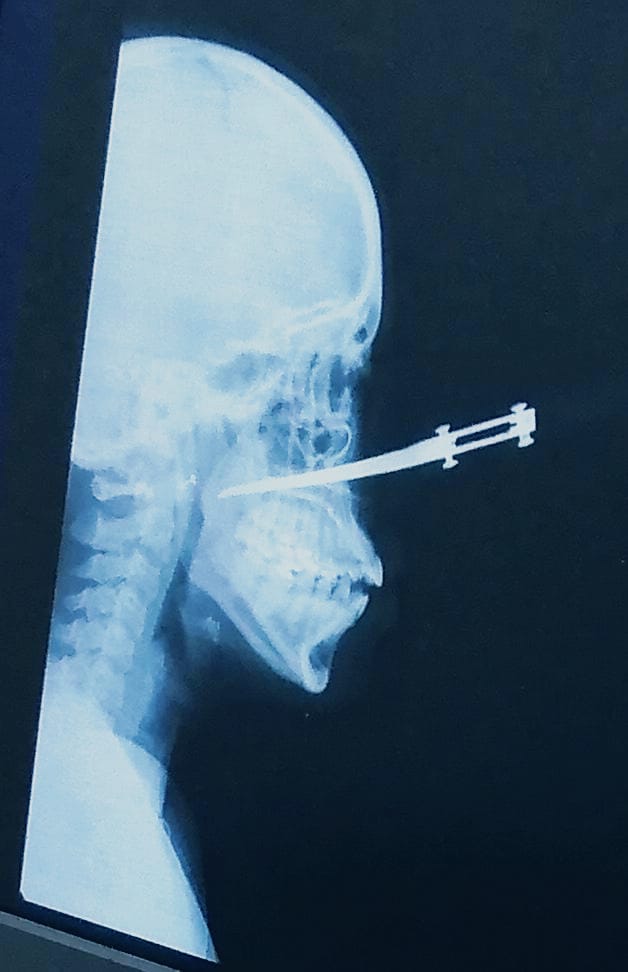

Casi matan a una mujer por robarla, el cuchillo le quedó incrustado en el rostro

Por fortuna Yoleydis Montaban Hernández, de 35 años, está viva para contar los hechos que hoy la tienen recluida en un centro asistencial de Cartagena con un cuchillo incrustado en su rostro, que le dejaron delincuentes que intentaron robarla en el barrio El Pozón, momentos en que se dirigía a su lugar de trabajo.

Dijo que, “la primera reacción de uno es defenderse, inmediatamente me mandaron a mi un machetazo, mi hija metió la mano para evitar que me dieran y le dieron a ella fue en la mano, le cortaron dos dedos, afortunadamente no se lo rebanaron si no que fueron cortadas. Luego el otro el que tenía el cuchillito se le abalanzó fue a ella y le enterró el cuchillo en la cara”.

“No había ni a quien pedirle auxilio porque las calles estaban solas, mi hija afortunadamente podía caminar y llegamos al Hospital que nos quedaba a dos cuadras y allí el personal médico dijeron que el caso no era ahí, llamaron una ambulancia y nos llevaron al lugar donde la atendieron. Tiene otra herida en el cachete del mismo lado donde le incrustaron el cuchillo”, sostuvo Humberto Montalban.

Por la nariz le entró el cuchillo, eso era muy delgadito, afortunadamente no le llegó a la columna, el cuchillo le llegó hasta un poquito más allá de la garganta, pero por fortuna no le dañó ningún órgano. Me siento impotente, sentí ganas de correr tras ellos para que me mataran, pero era más importante atender a mi hija. Ellos salieron caminando rápido, inmediato salieron de la otra cuadra se perdieron, no nos quitaron nada de valor”, argumentó Humberto.